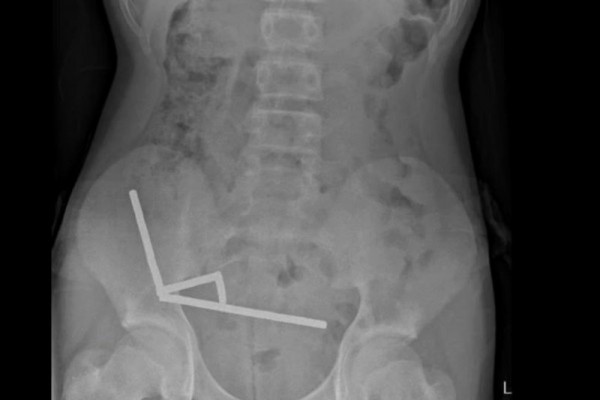

A 13-year-old boy in New Zealand needed emergency surgery and lost part of his bowel after swallowing more than 80 small, high-powered magnets, doctors said. Photo courtesy of the New Zealand Medical Journal

Scans showed that the magnets had formed four chains inside his abdomen, binding parts of the bowel together.